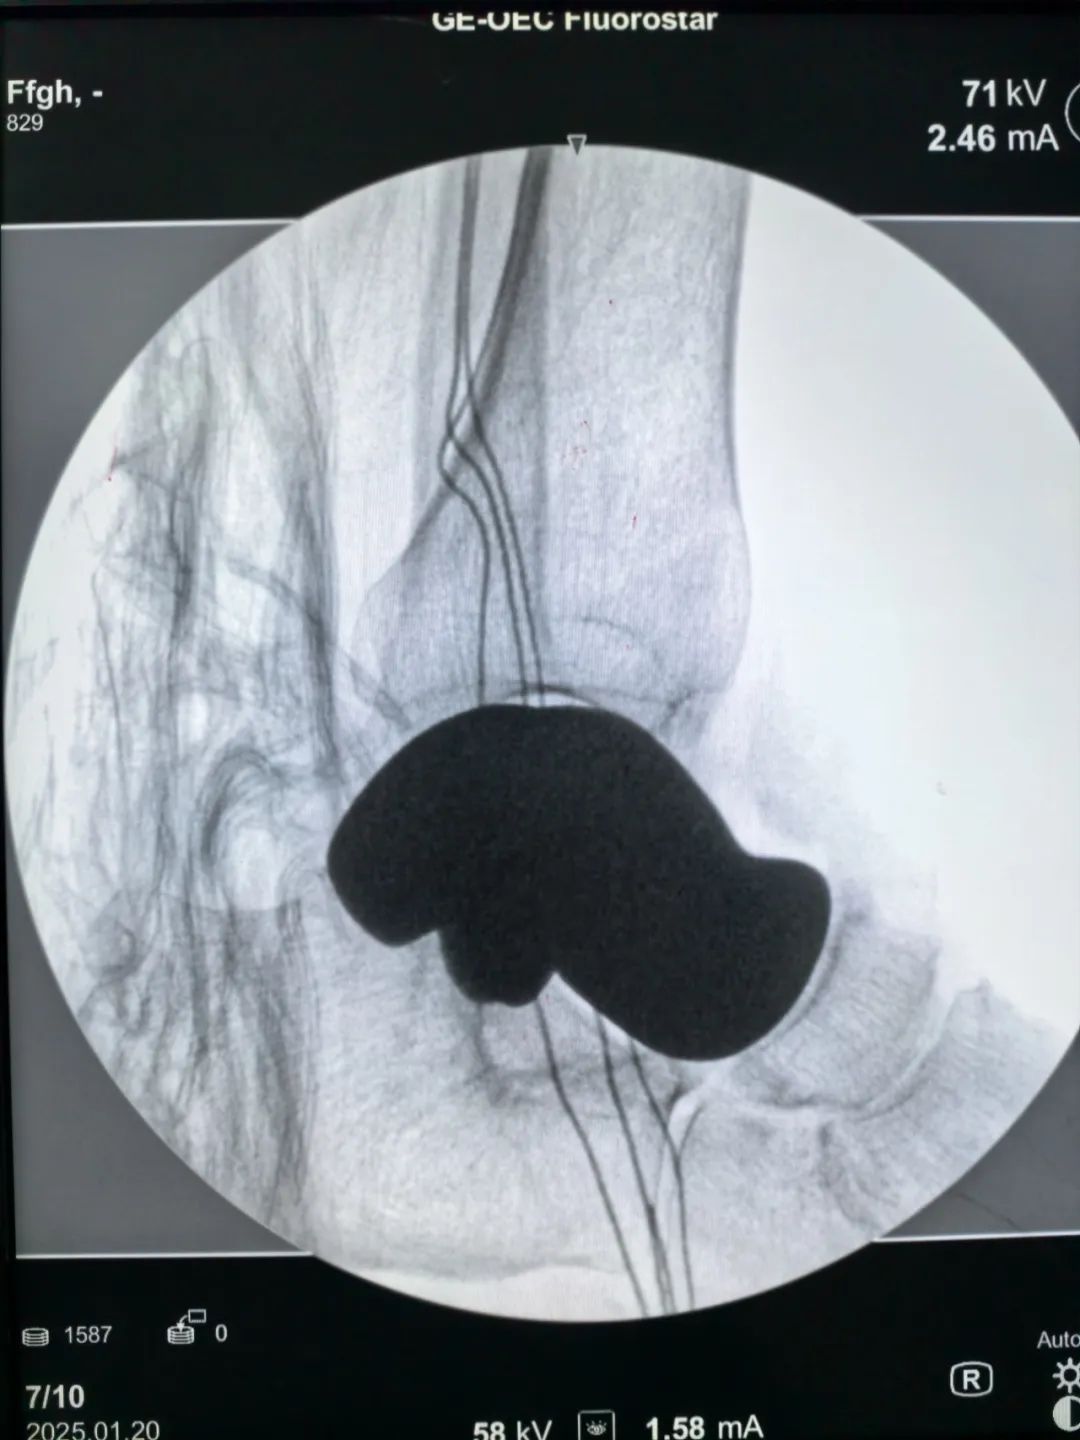

“我们通过3D建模技术,对患者的距骨进行1:1数字化复刻,结合生物力学分析精准计算骨骼的生理曲度、受力点等参数,最终定制出与患者结构完美契合的专属假体。”江川区医共体总医院骨科主任杨勇介绍说,作为人体足部的“承重枢纽”,距骨承担着缓冲震荡、维持平衡的关键功能,一旦发生严重坏死或损伤,传统治疗手段往往面临假体适配难、术后恢复差等困境。尤其是传统的距骨假体往往是标准化生产,难以满足每个患者的个性化需求。而3D 打印的假体能够精准匹配患者的骨骼结构,大大减少了手术过程中对周围组织的损伤,同时也提高了假体的稳定性和使用寿命。

今年1月,在云南省第一人民医院专家团队的全程指导与紧密协作下,江川区医共体总医院骨科团队凭借精湛技艺,将经过精密打印、毫米级误差校准的全距骨假体,稳稳植入到郑阿姨体内。